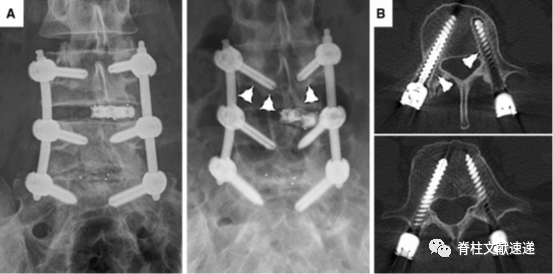

本文作者独辟蹊径的研究了经皮螺钉松动的危险因素,通过对32例患者进行术中导航经皮置钉,并根据螺钉是否松动分为两组,在手术后即刻及术后1年进行CT评估以确定相关危险因素。

作者发现螺钉松动组的残障指数和疼痛评分明显更高,这与开放螺钉的研究结果较为一致。安放连接棒后,如果发生螺钉有效长度减少(即刻的拔钉),术后远期出现螺钉松动的风险更大,另外经皮螺钉外倾角过小也是经皮螺钉松动的主要危险因素。笔者在进行经皮螺钉固定中也体会到,经皮螺钉的进钉点与常规开放置钉相比较为偏外,从而需要更大的外倾角度,外倾不足可能出现螺钉远端穿出椎体的情况,长期来看也更容易发生螺钉松动。

图A和B为水平位外倾角和矢状位夹角;图C为术中即刻CT及术后CT